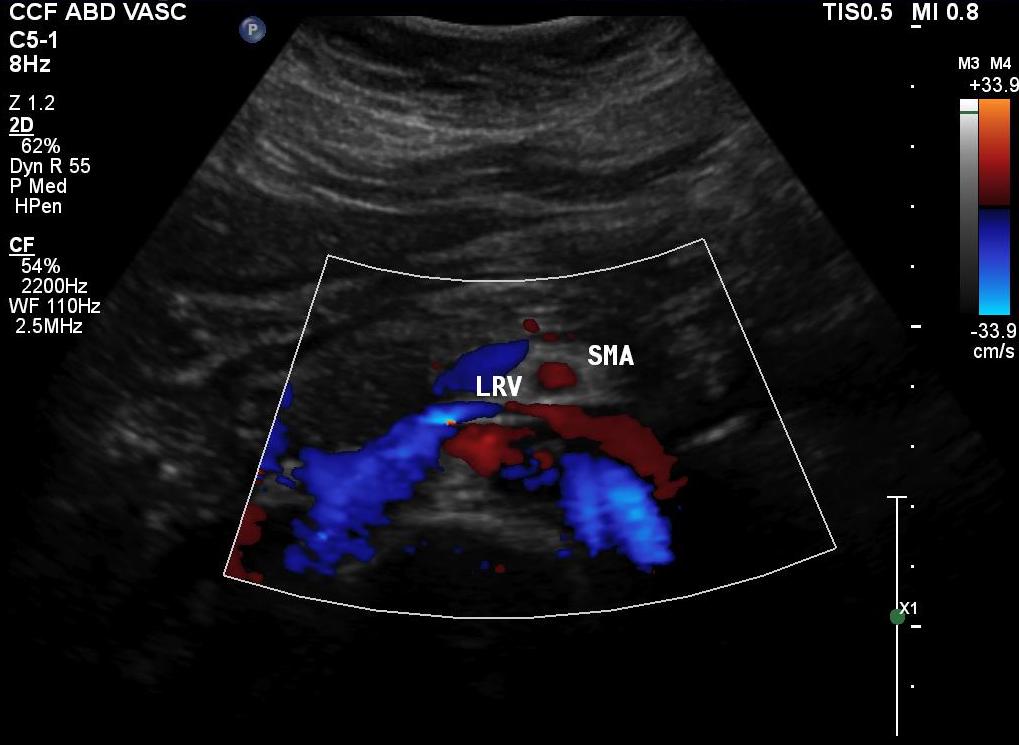

Duplex showed the narrowing in the left renal vein and spectral Doppler showed elevated velocities across the compression caused by the superior mesenteric artery (below). The collecting system was not obstructed.

A history of left sided abdominal pain, flank pain, nausea, vomiting, associated pelvic pain, and episodes of hematuria are diagnostic. Examination is typically positive for left renal tenderness and flank tenderness. Laboratory examination include urinalysis for hematuria. Duplex, while technically challenging, will show renal venous compression with velocity elevation or loss of respirophasicity, CTA will typically show obstruction of the left renal vein with filling of collaterals, as will MRV.

On the duplex, the proximal left renal vein (LRV) was not visualized. The right kidney had normal parenchymal appearance and blood flows, while the left, the kidney appeared distended and had flows consistent with outflow obstruction.

spectral kidneys

Spectral Doppler flows show respirophasicity in right renal vein(RRV), outflow obstruction on left renal vein (LRV)